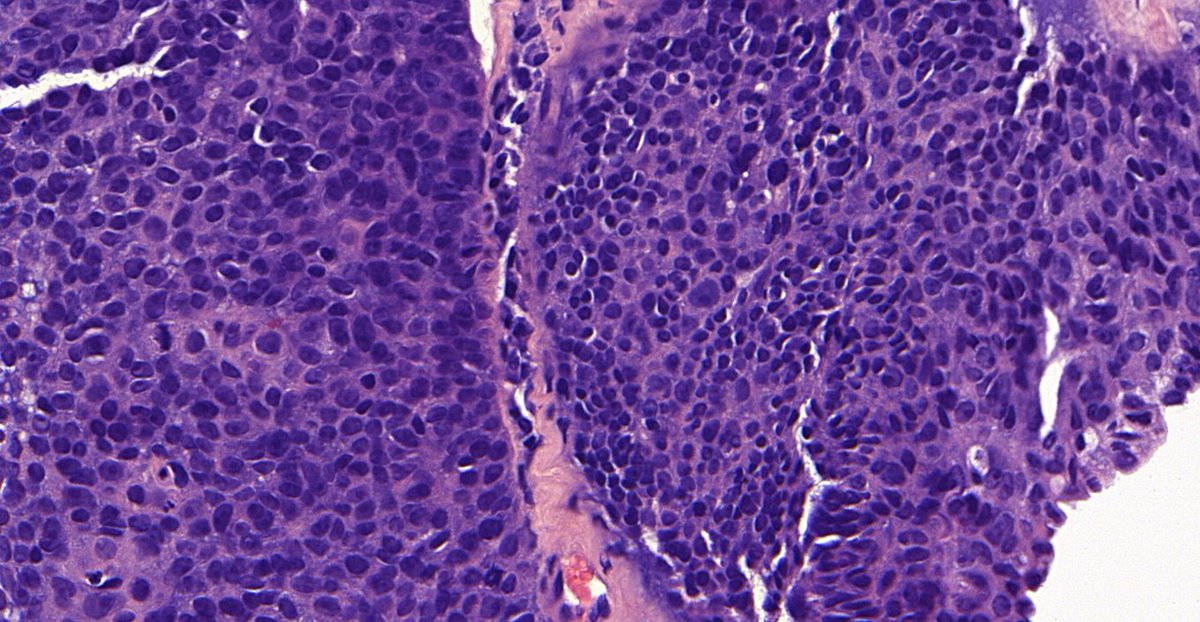

Thymic carcinoma

3/ These tumour tend to lose their immature lymphocyte population (i.e. the ability to “nurture” immature T-cells).

4/ Thymic ca also express CD5 and CD117, which are rare in thymomas (beware that CD117 can stain other tumours, including germinomas). https://www.ncbi.nlm.nih.gov/pmc/articles/PMC4503108/